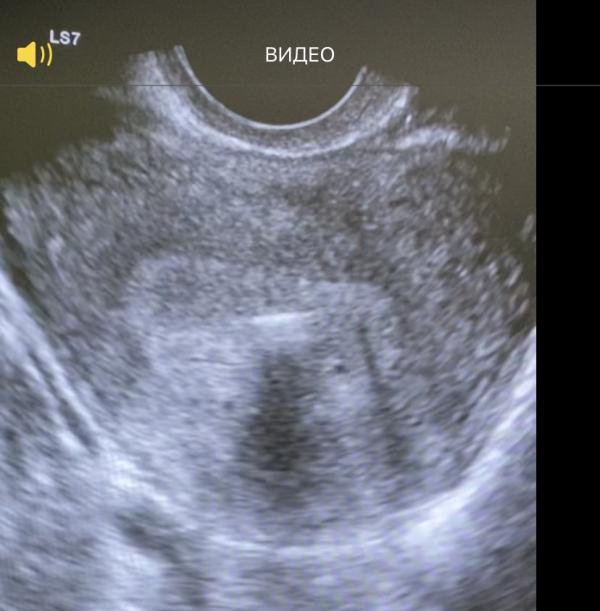

При проведении УЗИ : яичники без патологии ,желтое тело в правом яичнике, в полости матки определяется поперечно расположенная спираль, которая проникала в стенку матки ( справа) . Но это ещё не всё 🙂

По заднему листу эндометрия определяется плодное яйцо небольшого размера ( 4мм на втором фото)